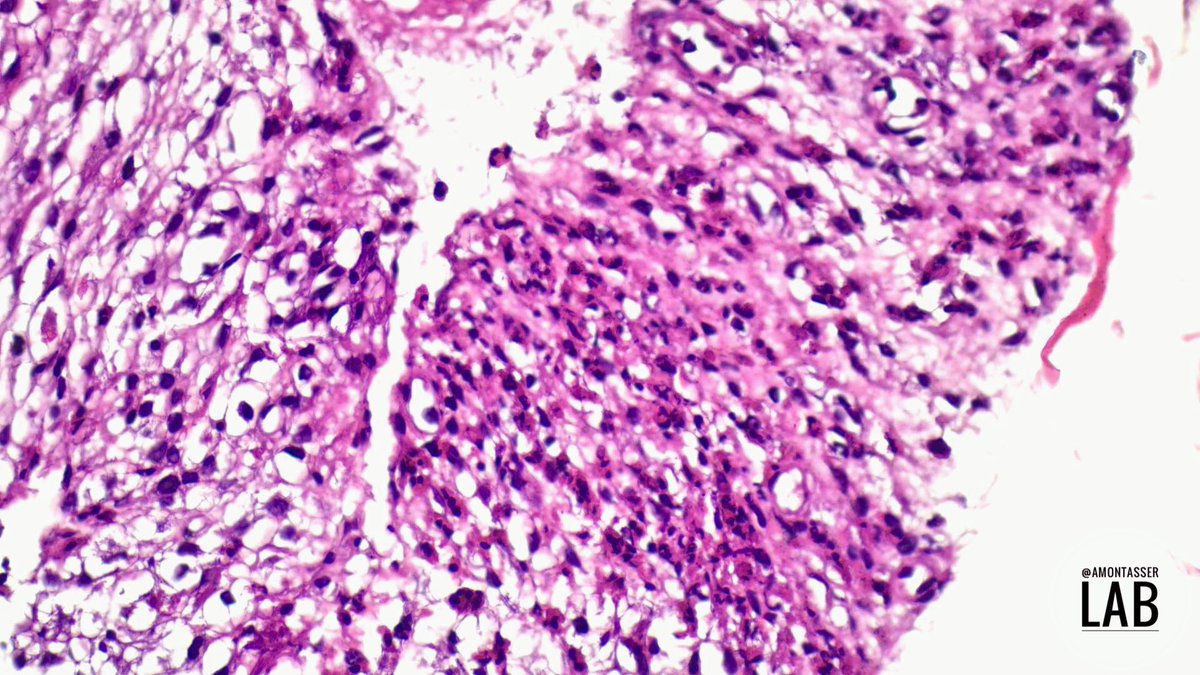

Weekend and Eid vacation so time for an easy #PathGame 🎱 Created this cellblock of EUS-FNB material obtained from a lower esophageal / cardia submucosal swelling of < 3 cm. I made my mind on HE, and ordered 3 immunostains for confirmation ; alphabetically CD34, KIT and SMA 🤓

Weekend and Eid vacation so time for an easy #PathGame 🎱

Created this cellblock of EUS-FNB material obtained from a lower esophageal / cardia submucosal swelling of &lt; 3 cm.

I made my mind on HE, and ordered 3 immunostains for confirmation ; alphabetically CD34, KIT and SMA 🤓